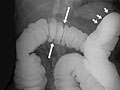

• In a double-contrast or air-contrast study, the colon is first filled with barium, and then the barium is drained out. This leaves only a thin layer of barium on the wall of the colon. The colon is then filled with air. This provides a detailed view of the inner surface of the colon. It makes it easier to see narrowed areas (strictures), diverticula, and swelling.

• Find problems with the structure of the large intestine. Problems may include narrowed areas (strictures) or pockets or sacs (diverticula) in the intestinal wall.

• Sacs in the colon wall (diverticulosis).